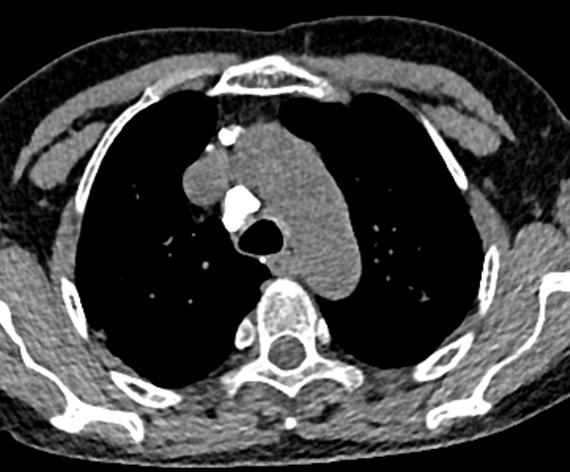

图1~图7 胸部CT示双肺多发钙化

问题在哪儿?

肺部钙化灶脱落,掉进左主支气管(图8),因为钙化病灶是坚硬的、锐利的,就像一个石头在不断地刺激支气管粘膜,导致患者咳嗽。

图8 胸部CT